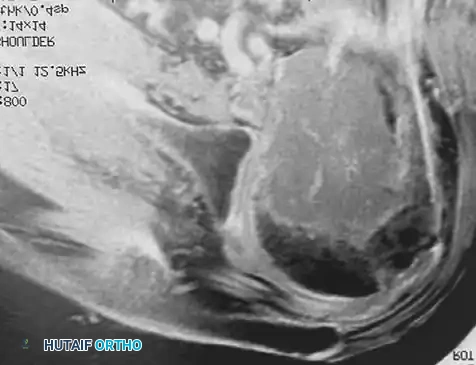

3. Acetabular and Pelvic Reconstruction

Metastatic destruction of the acetabulum presents a complex biomechanical challenge. The Harrington classification is often used to guide reconstruction. For significant cavitary defects with medial wall or column compromise, the lesion is curetted, and the structural integrity of the pelvis is rebuilt using threaded Steinmann pins or an acetabular reinforcement cage, heavily augmented with PMMA.

Fig. 22-23: (A, B) Radiograph and CT of a 66-year-old man with metastatic lung cancer destroying the right acetabular posterior column and wall. Preoperative embolization was performed to minimize blood loss. (C) Intraoperative view after curettage. Guidewires were placed from the defect to the posterior ilium and anterior iliac crest. Cannulated screws were placed over the wires to support the cement mantle. (D) An acetabular cage was placed, and the defect was filled with PMMA as the cup was cemented. (E) Postoperative radiograph demonstrating a stable construct.